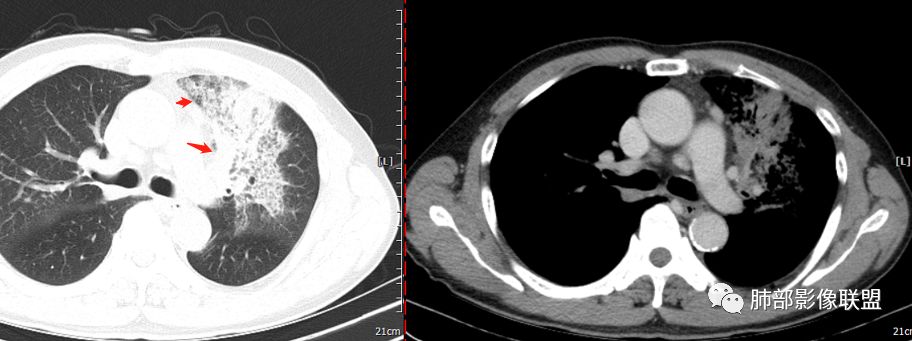

背段支气管有问题,局部有结节

左肺上叶病灶长轴与支气管走形一致,提示沿支气管分布病变,倾向于炎性,大家可能怀疑这个病例是来源于胸膜下为主的,胸膜下来源首先整体是来源于胸膜下,与胸膜下之间没有间隙,而这例与胸膜下有间隙。而且这个病变是沿支气管朝外蔓延的,而胸膜下来源的是朝内蔓延的,唯一给我们错觉的是靠近纵隔胸膜这个地方有问题。但是靠近纵隔胸膜这个位置实变不是靠近胸膜实变,它边缘收缩的,没有膨隆的迹象。我们看到里面支气管直达远端稍扩张,是以中央间质为主、小叶间隔朝外蔓延,有间质也有实质病变,走向是沿中央间质方向走的,我个人倾向炎性病变。    问题是右下叶病灶怎么解释?右隔上、右肺门各有一个结节。这个病人有急性咳嗽、胸痛的病史,还有糖尿病病史,周围渗出比较明显,应该警惕炎性病变,要警惕克雷伯杆菌、结核、金葡菌霉菌,因为糖尿病人经常好发这些病菌感染。那么右下叶病变怎么考虑?能不能一元论?    左肺病灶是一个急性渗出为主的病变,一个急性感染的迹象;右肺下叶背段结节,没有看到支气管,增强图支气管壁增厚,局部小结节,呈分叶状,支气管堵塞,没有粘液栓样指套样改变,但是里面有强化,我倾向于癌,其次待排结核。我还是倾向于癌的可能性,恶性可能性大一些,可惜我看不到支气管腔内。还考虑有没有淀粉样变性的问题,弥漫钙化灶最常见的一个是结核,另一个是淀粉样变性。叶段支气管壁有弥漫增厚的迹象。所以淀粉样变性跟结核都要考虑。

吴老师标记的这个支气管结节有点意思。其他的真是想不到鳞癌

回头看尖段的分支和背段肯定是堵了,两处应该都是鳞癌,右肺基底段的就不知道了。

支气管镜下明显见到新生物了,病理取到表面粘膜。

鳞癌起源于支气管粘膜,是气道中最常见的恶性肿瘤,易造成支管壁增厚,并突入腔内形成结节,造成狭窄、阻塞或截断;早期鳞癌表现为沿支气管生长的梭形结节或局限性增厚,辖区内常出现阻塞性炎症,这样的病灶赢多平面重建并仔细观察支气管改变;如果有支气管壁偏心性增厚伴管腔狭窄或腔内结节形成,都要想到早期鳞癌的可能性,复查或内窥镜检查是必要的。

鳞癌好发于中老年人,与吸烟关系密切,如果发现不易吸收的,或同一部位反复无常局限性肺炎,我们应当仔细观察支气管壁的病变除外阻塞的可能;该病例右肺下叶背段及左肺上叶支气管有肿块及管壁的增厚,应当想到恶性可能。

1.右肺下叶支气管壁增厚,后壁为主,且显示壁外结节,未见异常强化。这样的结节和蔓延方式一般会高度怀疑气道来源的恶性肿瘤,如鳞癌、粘液表皮样癌、腺样囊性癌等。可惜没有相应病理学资料支持。

3.我们都注意到患者左肺上叶支气管开口的改变,这种改变有可能会用常见的“肉芽肿性炎”或“分泌物”加以解释,因管腔内的隆起部分未能观察到强化,管壁外未见相应快影或结节影。

熟料问题恰恰出在这里!它没能引起完全阻塞,未能形成“S”形肺不张。

该病例非常值得我们警醒,忽略支气管管腔内的任何异常都可能大意失荆州!